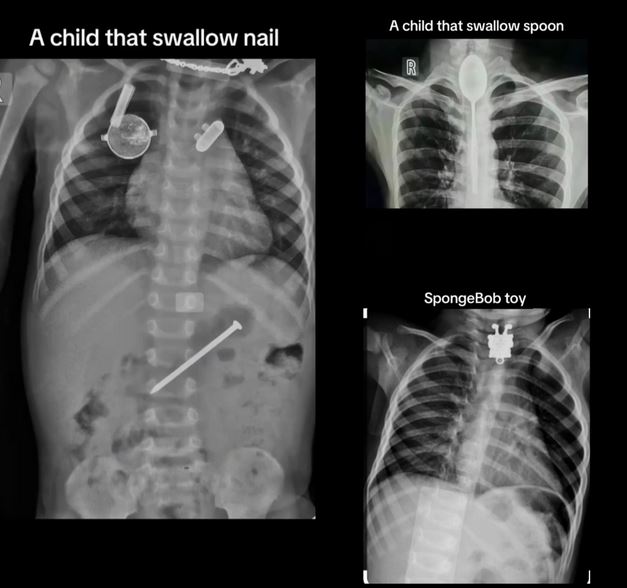

A Nigerian medical doctor has shared some of the cases he witnessed while working in a pediatric clinic for 24 hours.

The doctor, who goes by @chacho1 on TikTok, shared the video with the caption: "How working 24 hours in pediatric clinic looks like."

The video showed X-rays of different children, including one who swallowed a spoon.

Other items swallowed by different kids include: safety pin, toys, key, nail, coin, zip.